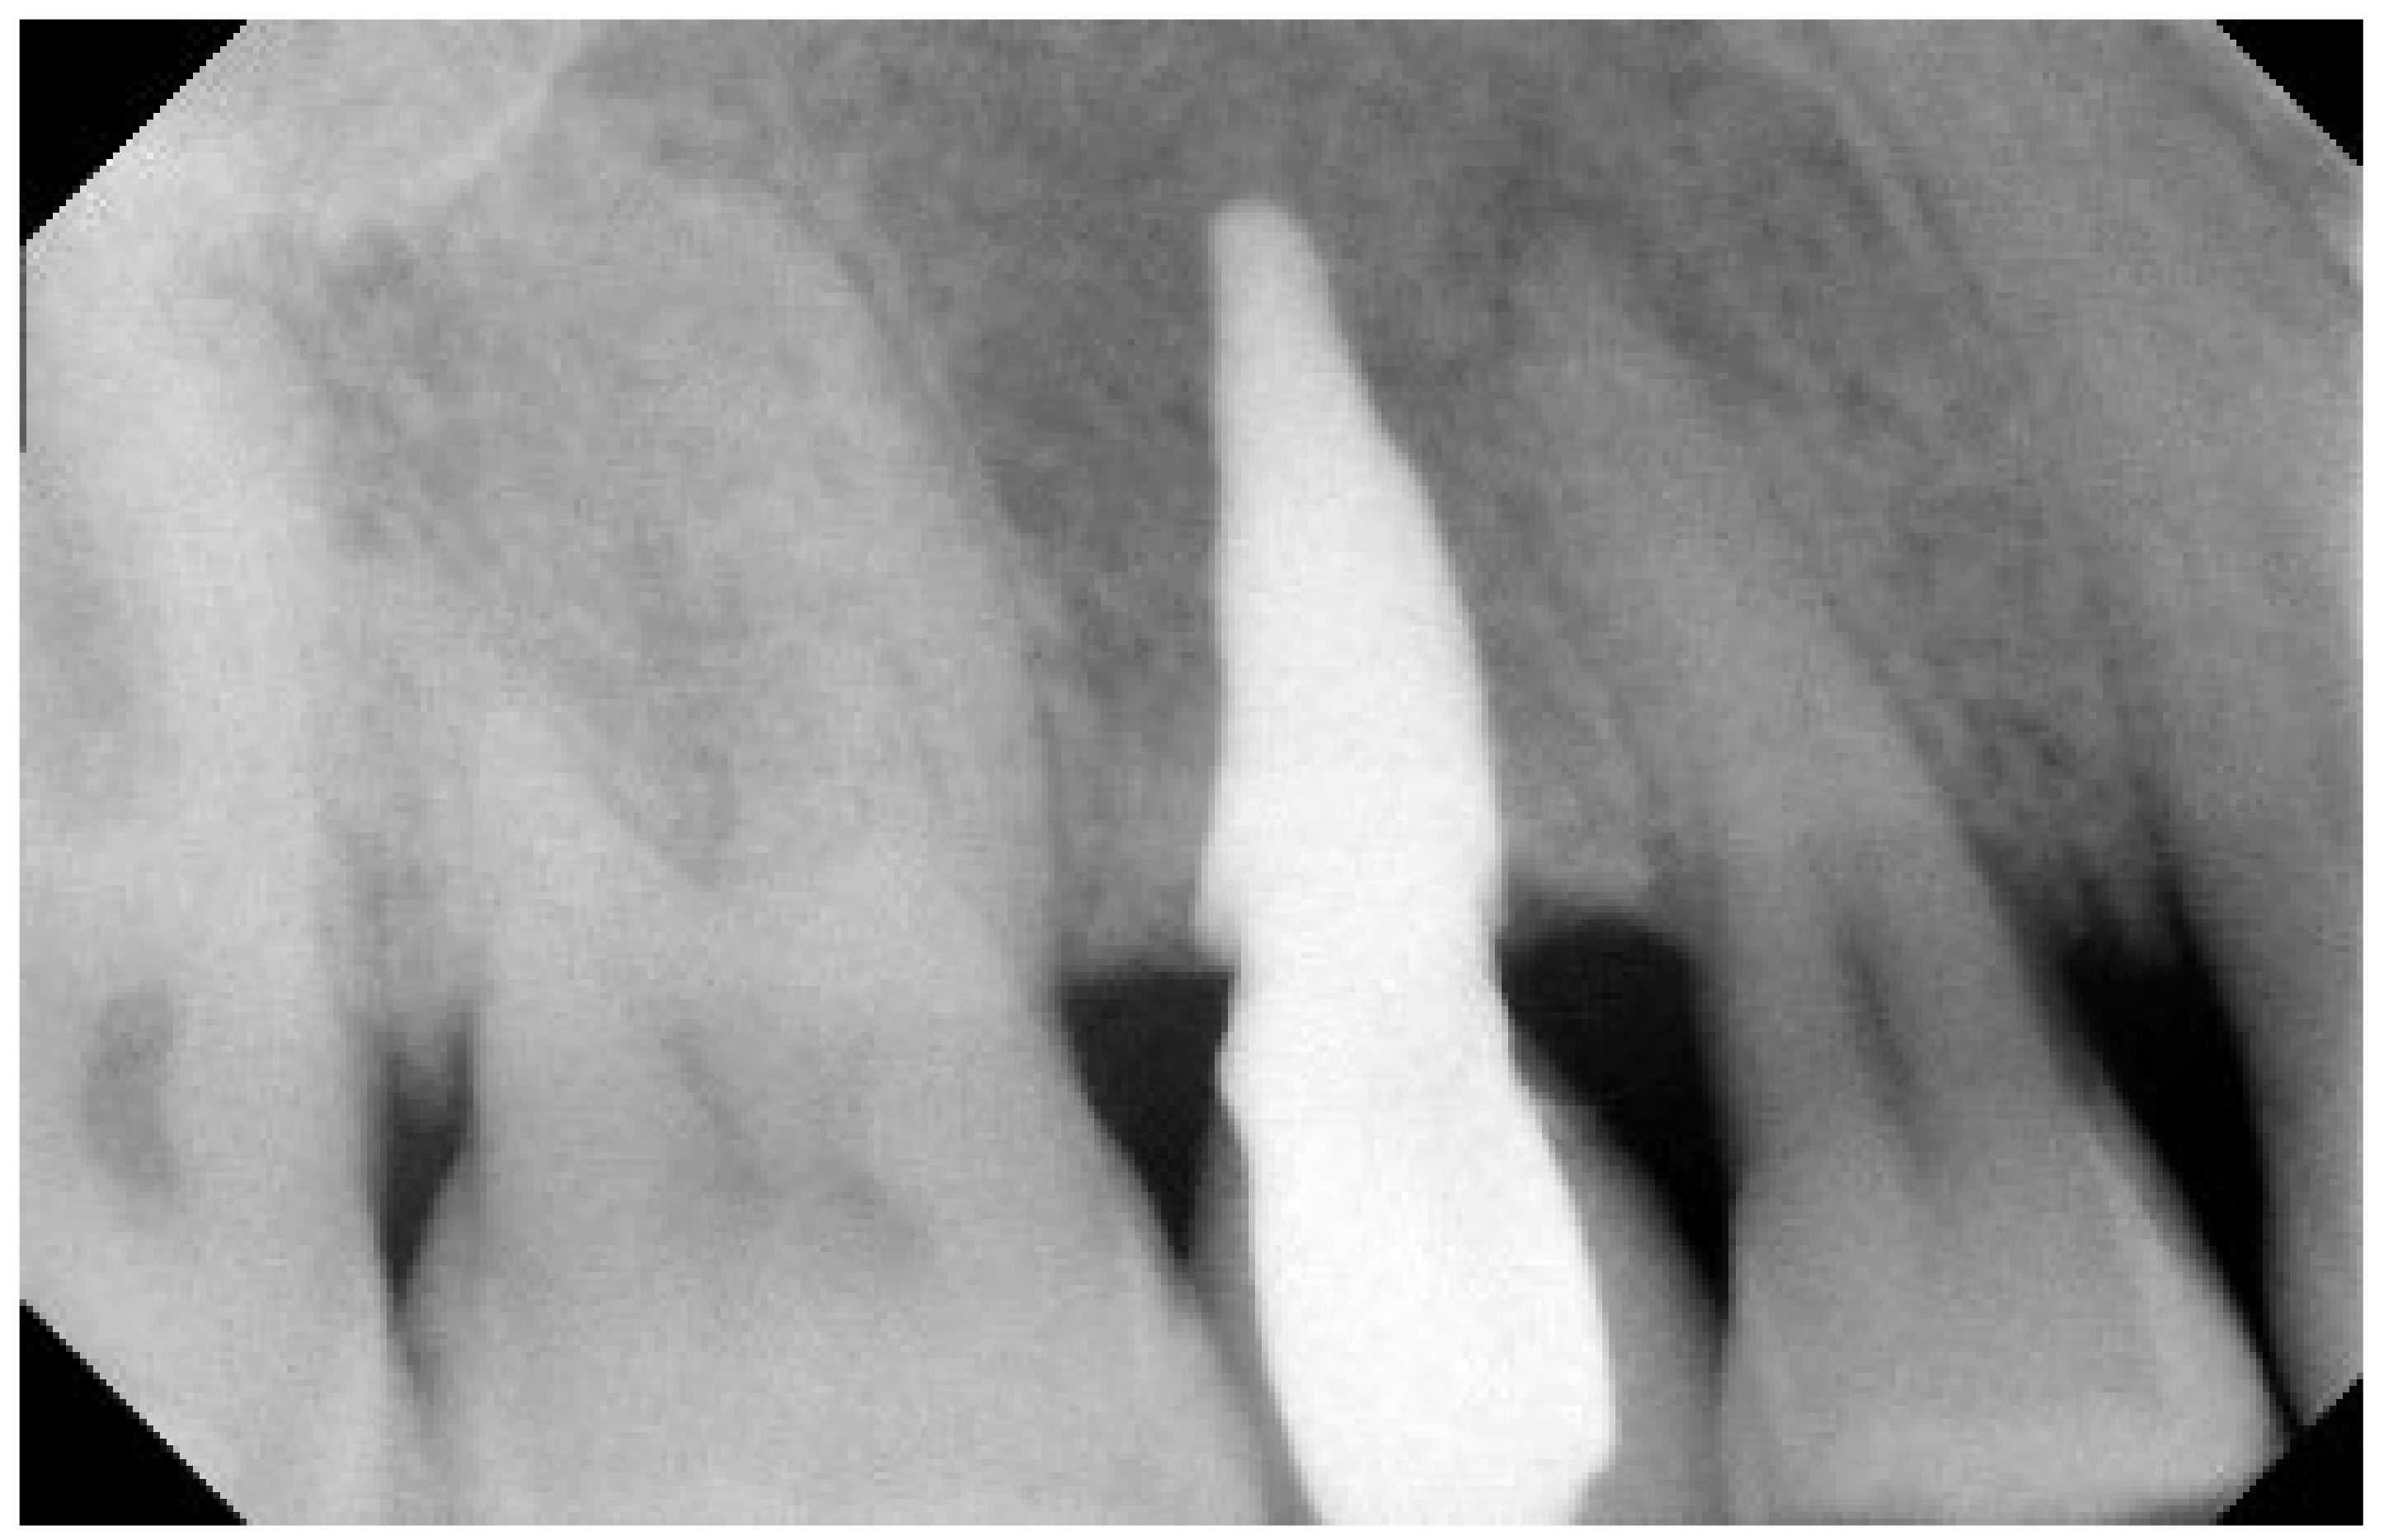

3. Results